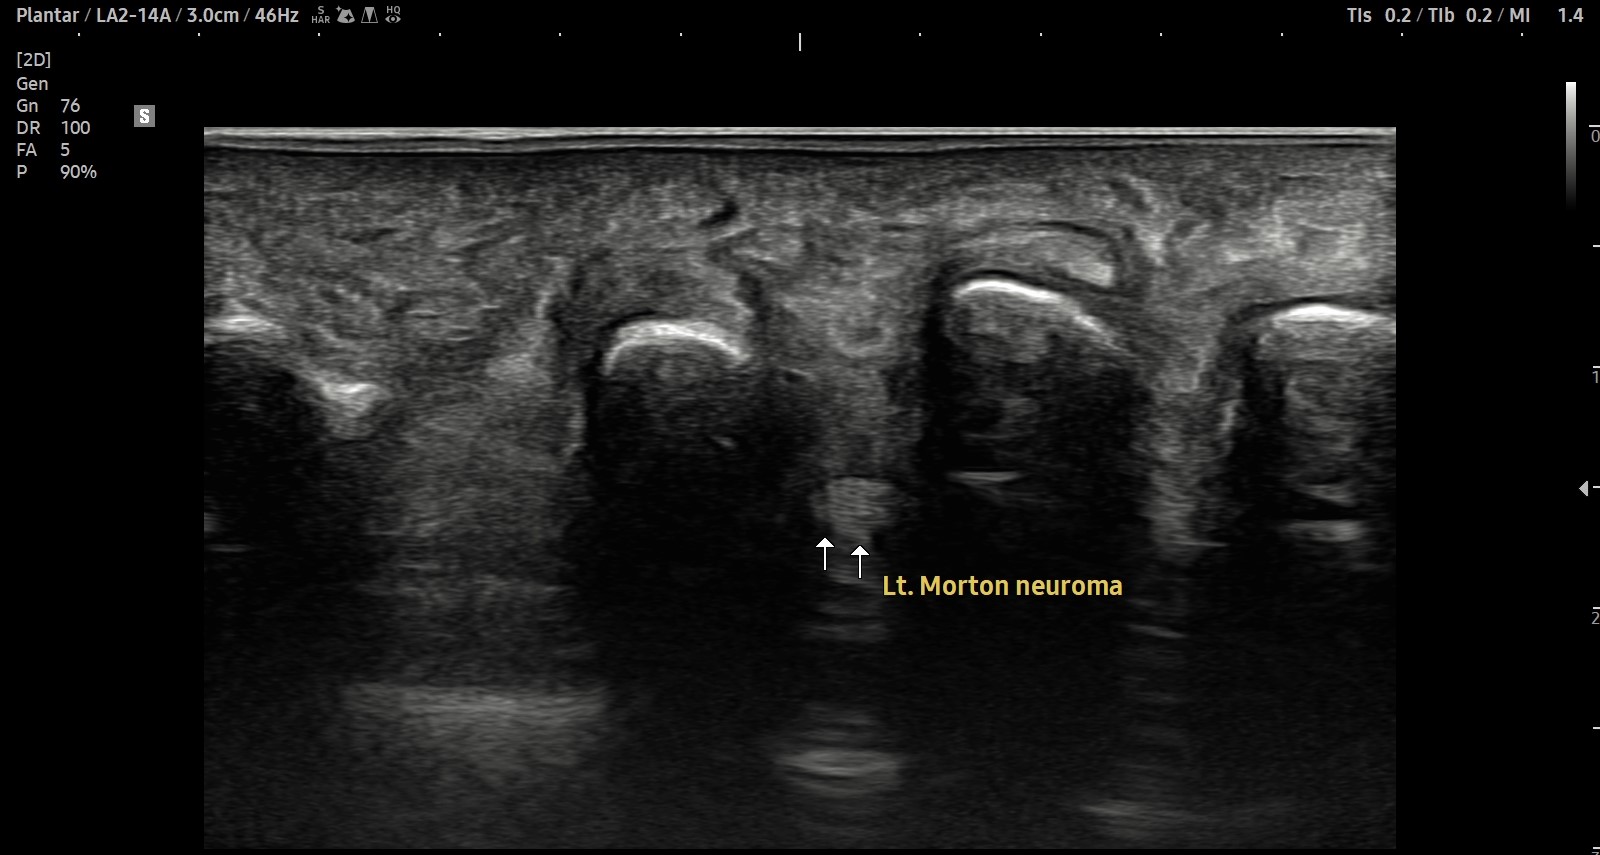

- 치료기간 : 2025. 7 . 4 ~ 2025 . 9 .1

- 치료횟수 : 10 회 (2cycle)

치료 전

치료 후